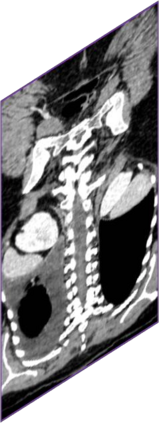

Due to the constraints of the imaging device and high cost in operation time, computer tomography (CT) scans are usually acquired with low intra-slice resolution. Improving the intra-slice resolution is beneficial to the disease diagnosis for both human experts and computer-aided systems. To this end, this paper builds a novel medical slice synthesis to increase the between-slice resolution. Considering that the ground-truth intermediate medical slices are always absent in clinical practice, we introduce the incremental cross-view mutual distillation strategy to accomplish this task in the self-supervised learning manner. Specifically, we model this problem from three different views: slice-wise interpolation from axial view and pixel-wise interpolation from coronal and sagittal views. Under this circumstance, the models learned from different views can distill valuable knowledge to guide the learning processes of each other. We can repeat this process to make the models synthesize intermediate slice data with increasing inter-slice resolution. To demonstrate the effectiveness of the proposed approach, we conduct comprehensive experiments on a large-scale CT dataset. Quantitative and qualitative comparison results show that our method outperforms state-of-the-art algorithms by clear margins.